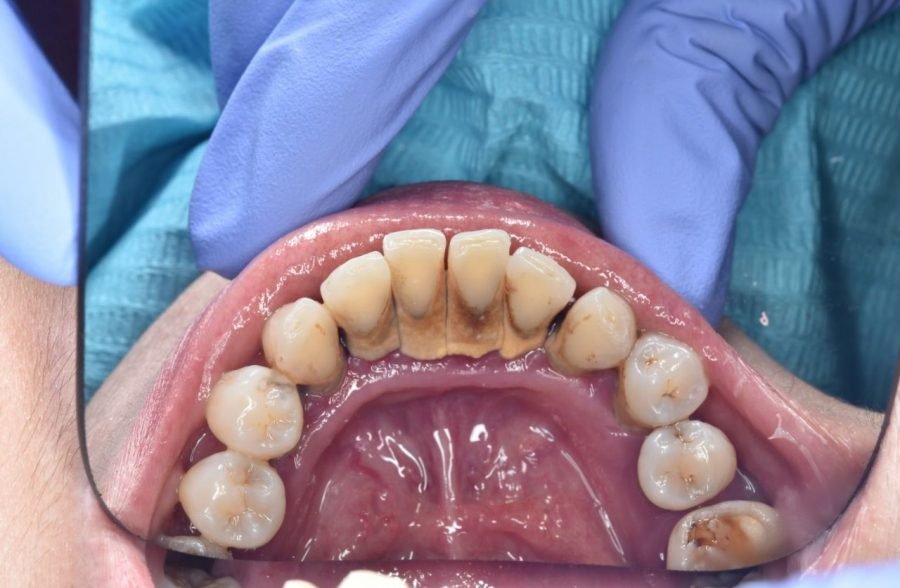

KENAPA KITA HARUS RUTIN MELAKUKAN SCALING GIGI? Gigi yang sehat dan bersih tentu membuat Anda lebih percaya diri, bukan? Namun agar senantiasa sehat dan bersih, sikat gigi saja tidak cukup. Scaling adalah perawatan gigi yang sebaiknya rutin anda lakukan APA ITU SCALING GIGI? Scaling gigi adalah prosedur pembersihan karang gigi dengan menggunakan alat khusus yang dilakukan […]